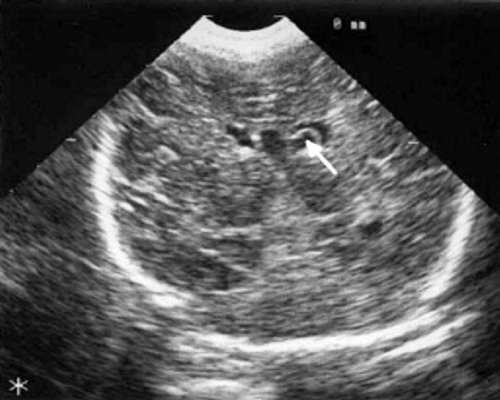

При эхоэнцефалографии у детей I группы выявлено от 1 до 3 изолированных кистозных структур (не сочетающихся с другими структурными изменениями) диаметром от 0,2-0,5 см (рис. 1, 2), расположенных в верхушке или теле сосудистого сплетения левого бокового желудочка. У 3-х из этих детей исходные данные вентрикулометрии соответствовали нормальным значениям. У 1-го ребенка отмечено незначительное (до 0,6 см) расширение межполушарной щели и субарахноидальных пространств по конвекситальной поверхности мозга и умеренное симметричное увеличение ширины лобных рогов (преимущественно) и высоты тел боковых желудочков (до 0,7 см).

Рис. 1. Эхоэнцефалограмма ребенка Р. со смешанной герпес-цитомегаловирусной инфекцией, 7-е сут. жизни. Стрелками обозначена киста в верхушке сосудистого сплетения левого бокового желудочка.